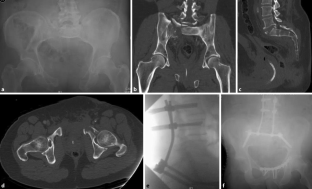

Abb. 2